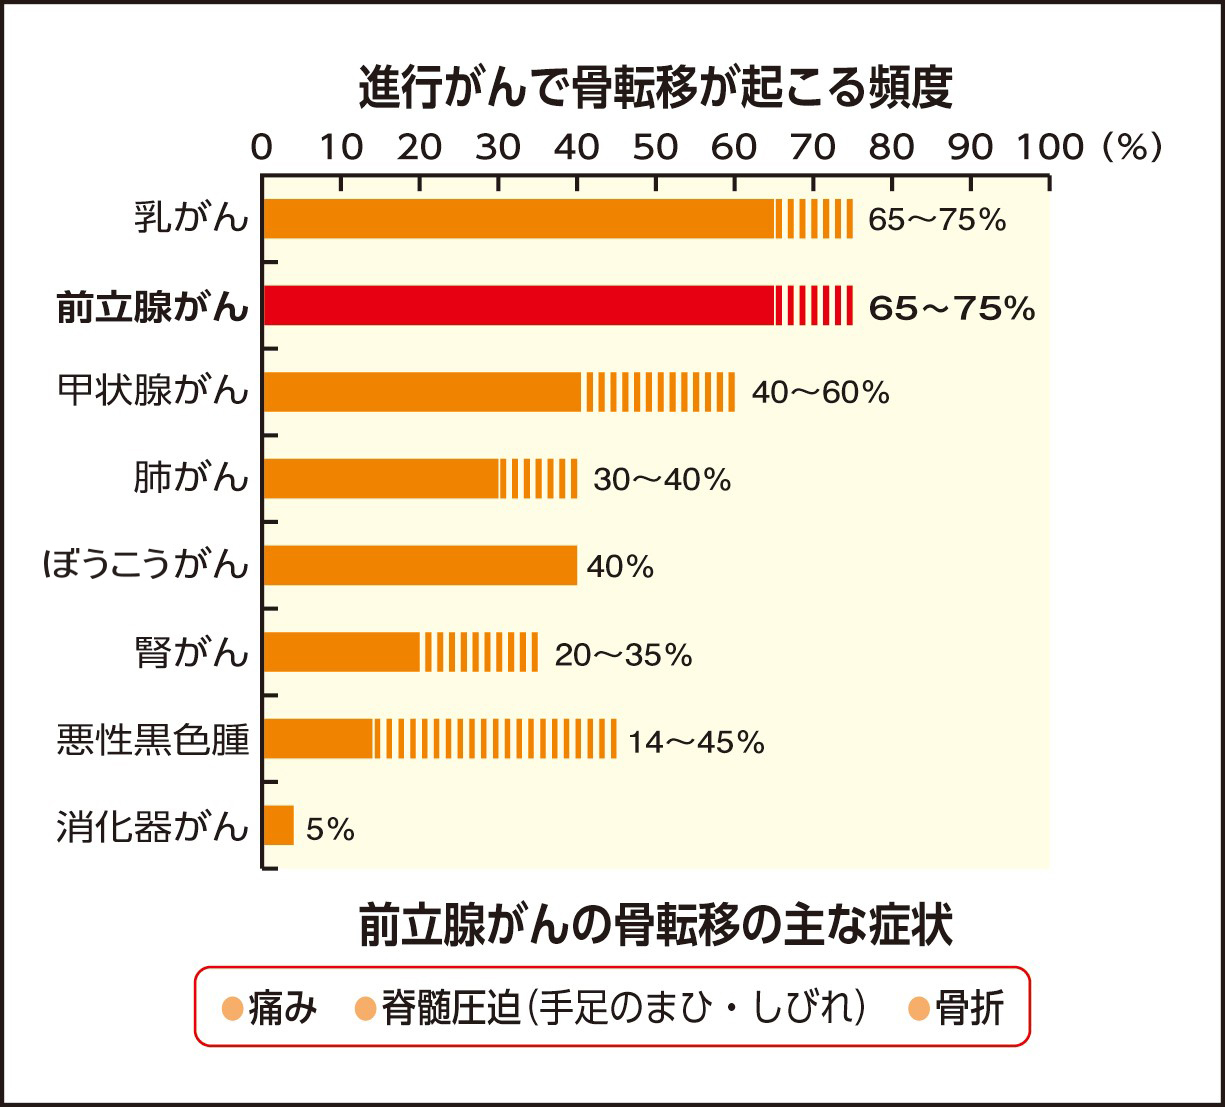

前立腺がんの骨転移治療の選択肢が拡大 医療ニュース トピックス